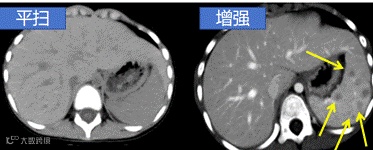

CT 增强是在 CT 平扫 的基础上,通过静脉注射含碘的造影剂,让血管、脏器、肿瘤等组织在影像上显示更清晰的一种检查方式。

✅ 病灶鉴别力强:能更好地区分炎症、肿瘤、囊肿

✅ 动态观察:动脉期、静脉期、延迟期多阶段成像,帮助医生全面分析